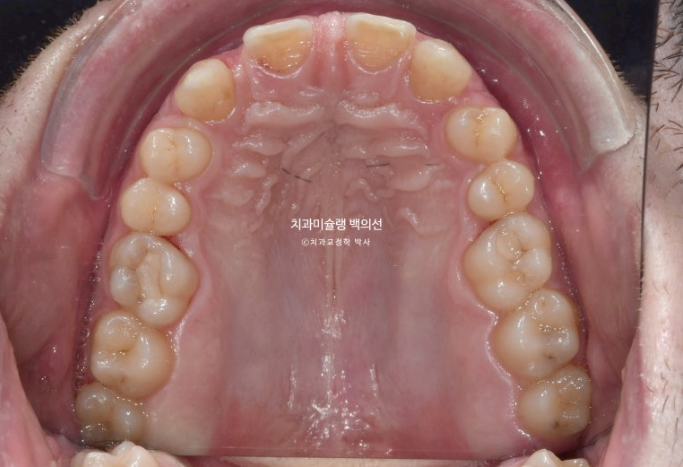

23년 10월, 9개월간 32개 장치를 모두 낀 후 모습입니다.

중절치 두 개 단차가 보입니다. 중심선이 약 1mm 안 맞습니다.

어금니 교합이 뜨는 부분이 있습니다.

배열은 좋습니다.

중심선 개선, 어금니 교합관계 개선, 쓰러진 앞니 뿌리각도 개선 등을 목표로 추가장치 제작에 들어갔습니다.